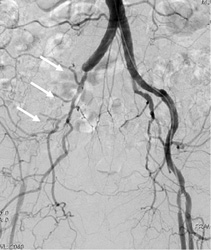

A woman in her 80s with intermittent claudication due to occlusion from the abdominal aorta to both iliac arteries

Stents were placed at the site of occlusion (indicated with arrows) located from the aorta to both common iliac arteries. Blood flow was successfully restored. Intermittent claudication in both feet resolved. The patient returned to her daily routine.